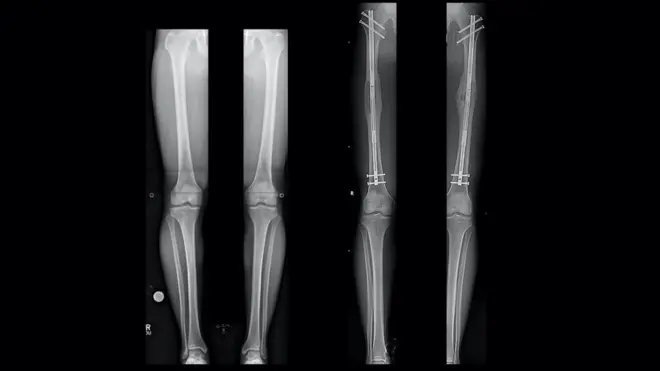

በህመምተኛው ግለሰብ ልብ ላይ በአንድ ጊዜ የተሰራው ሁለት ቀዶ ህክምና ሲሆን፣ አንደኛው የልብ የደም ቧንቧዎች በሚዘጉበት ጊዜ የደም ቧንቧን ከሌላ የሰውነት ክፍል በመውሰድ የተዘጋው ቦታ ላይ በመተካት የተከናወነ የልብ የደም ስር ነቅሎ መትከል (ሲኤቢጂ) ነው።

ሌላኛው ደግሞ 'ኦርቲክ ቫልቭ' ወይም ደግሞ አንደኛው የግራ የልብ ክፍል በር ሙሉ በሙሉ ተዘግቶ ደም ከቀኝ የልብ ክፍል ወደ አኦርታ (Aorta) መውጣት ሲቸገር የልብ በር ቀዶ ህክምና (ቫልቭ) የሚባለው ነው።